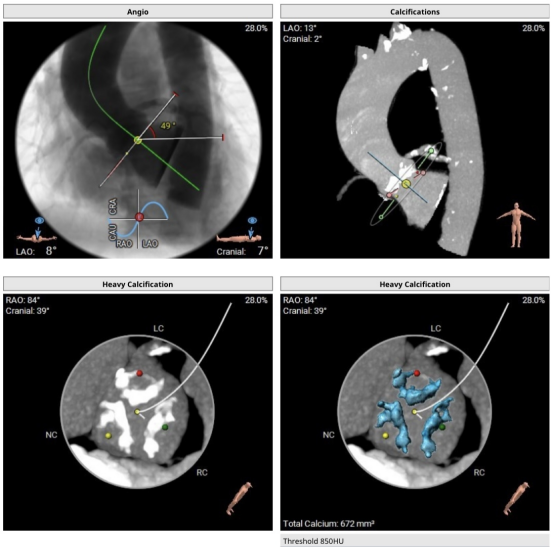

手术策略及过程

采用镇静加局麻的方式,经由右侧股动脉置入20F大鞘,20mm球囊扩张前测跨瓣压差80mmHg,选用MuguetA™ 23mm瓣膜,标准体积+1cc充盈,180bpm快速起搏下精准释放,手术位置理想(90/10%),主动脉根部造影提示微量瓣周漏,压差完全消失,冠脉开口通畅,心电图提示传导系统无影响,复查造影右股动脉未见明显狭窄,无造影剂外渗无夹层,手术效果良好。

释放

图片

造影

这款瓣膜为球囊扩张式瓣膜,其输送系统在推送瓣膜及调弯过弓性能方面,均表现流畅,输送系统进入到取出仅耗时11分钟。器械的显影环清晰,操作简单,定位精准,本例手术释放后瓣膜环上及环下高度比约为9:1。

对于本例手术而言,瓣膜尺寸及充盈体积的选择非常合适,瓣膜在释放后显示位置良好,术后测得压差完全消失,患者恢复良好,当天下地活动,术后1天顺利出院。